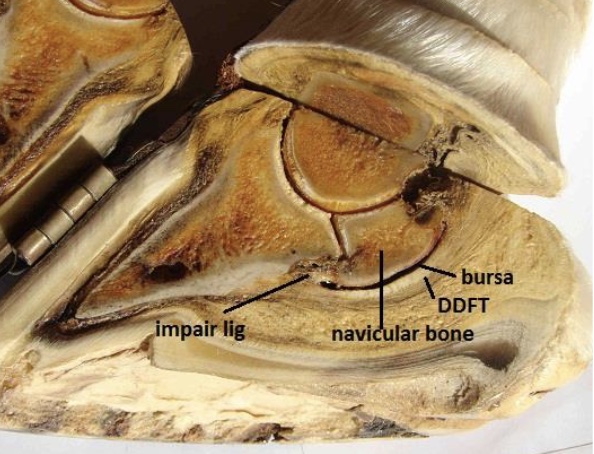

navicular disease

most common cause of chronic forelimb lameness

chronic degenerative condition of the navicular bone

-loss of medullary structure (+ lollipop synovial invaginations)

-bone sclerosis (hardening)

-enthesiophyte formation (excessive mineralization of soft tissue) on proximal and distal borders of the bone

-traumatic fibrilation of DDFT from contact w/ damaged flexor surface of the bone with adhesion formation btwn tendon and bone

penetrating wounds of the foot

anything towards the frog: BAD

ungual/collateral cartilage, DDFT sheath (synovial structure), DDFT, navicular bursa (synovial structure), navicular bone, distal interphalangeal joint (synovial structure) P3

if damage to synovial structure, risk of infxn arises & considered an emergency